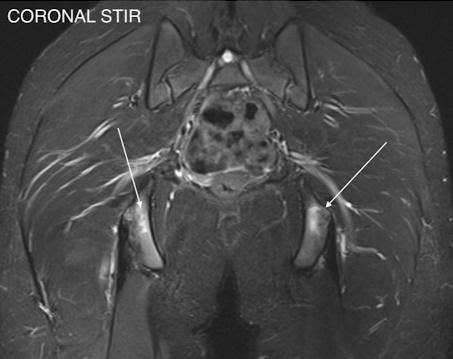

Mid teen footballer presenting with bilateral inferior gluteal, proximal hamstring and medial groin pain. This was accompanied with an increased training intensity with new step over and pivoting drills. MRI showed bilateral ischial apophysitis (bone marrow oedema arrowed in figure 6 and 7) and adductor origin inflammation (not shown).

Figure 6

Figure 7